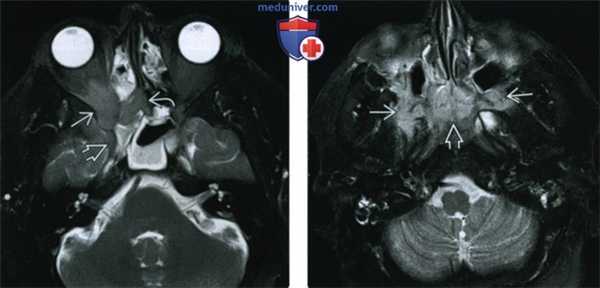

(Слева) При МРТ Т2ВИ FS в аксиальной проекции у этого же пациента определяется инфильтративное идиопатическое воспаление верхушки глазницы, решетчатого лабиринта и круглого отверстия. Гиперинтенсивные обтурированные пазухи легко отличимы от идиопатического воспалительного псевдотумора глазниц/внеглазничной локализации. Гипоинтенсивность обусловлена диффузным фиброзом, часто развивающимся в ткани обширного псевдотумора.

(Справа) При МРТ Т2ВИ FS в аксиальной проекции у этого же пациента определяется обширное внеглазничное идиопатическое воспаление, распространяющееся на крылонебные ямки и заднюю часть полости носа.